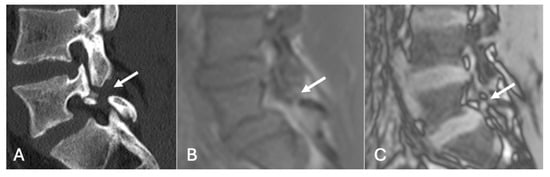

Figure 19.

Pars defect assessment CT image (A) and chemical shift in-phase (B) and out-of-phase (C), showing pars defect of L5 (arrow).

Figure 20.

Pars defect assessment sagittal CT image (A) and chemical shift in-phase (B) and out-of-phase (C), showing intact pars of L4 (arrow).

- On a slightly different theme, whilst not strictly utilising the SI drop-off calculations, chemical shift imaging in itself has been demonstrated to assess for and evaluate pars defects. In a cohort of 70 patients, chemical shift MRI effectively identified both intact and defective pars interarticularies, with out-of-phase imaging slightly better for detecting defects and in-phase imaging better for confirming intact pars. Although differences were not statistically significant, the technique demonstrated strong intra- and interobserver reliability and offers a fast, reliable complement to conventional MRI [41] (Figure 19 and Figure 20).